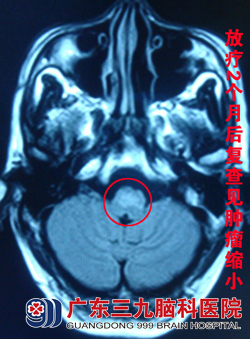

蔡林波主任查看其病情后,建议其首先予以手术探查,做活检以明确病理。但家属表示不愿意承担手术风险,选择直接行放化疗。4月9日,邓先生开始接受适形放疗及同步化疗。治疗1个多月后,邓先生病情逐步好转,走路不稳、视物重影等症状消失。治疗结束后两个月复查头颅MR 见脑干病变范围较前缩小,查体无明显阳性体征,邓先生一般情况良好,无不适。